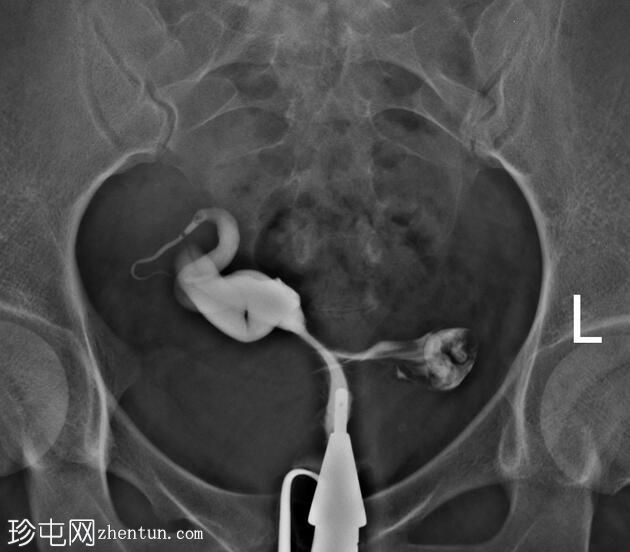

子宫体位于盆腔右侧旁中线,形态及轮廓正常。

宫颈管长度及黏膜表面正常,扩张正常。

右侧输卵管充盈,呈逐渐扩张,内有造影剂残留,无因输卵管积水导致的造影剂溢出。

左侧输卵管出现腹膜溢出。